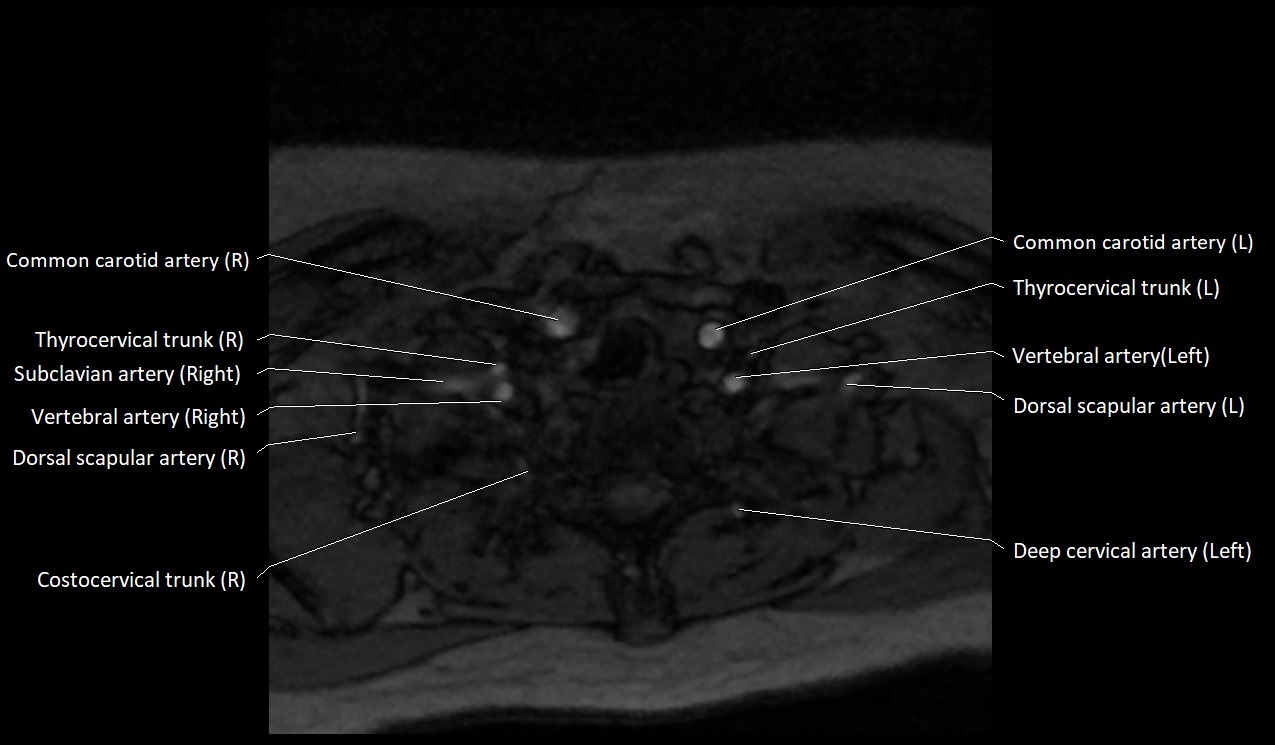

MRI images

image